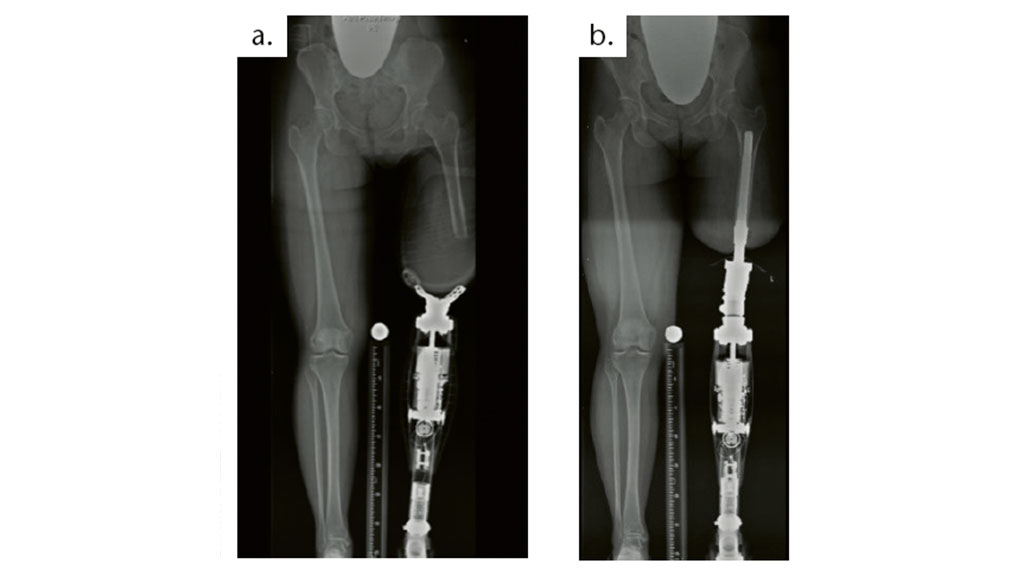

Besonders Doppelamputierte profitieren von osseointegrierten Systemen. Das Gewicht ist geringer als bei einer Schaftprothese, zudem behindern sich die Oberschenkelschäfte beim Gehen, Stehen und Sitzen nicht (Abb. 1).